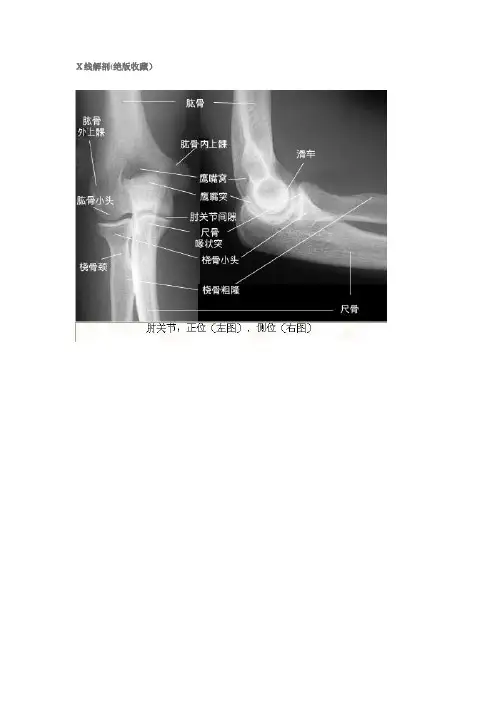

肘关节

正位(左图),侧位(右图)平片